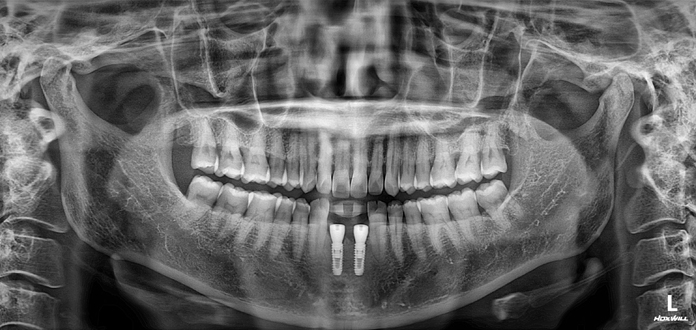

• Before

After